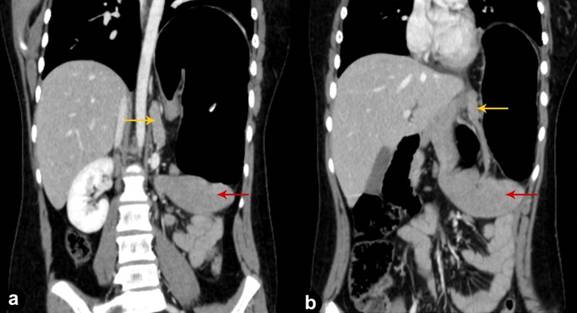

Figure 5. CECT abdomen, coronal reformatted images, show the presence of the wandering spleen (red arrows) and the pancreatic volvulus (yellow arrows). |

The stomach was decompressed using a Ryle’s tube. An emergency open laparotomy was performed which showed the stomach to be rotated in mesenteroaxial plane and confirmed the presence of the torsion in wandering spleen. No evidence of splenic or gastric infarction was noted. Derotation of the stomach, pancreas and spleen was performed. The diaphragmatic defect was repaired and gastropexy and splenopexy was performed.